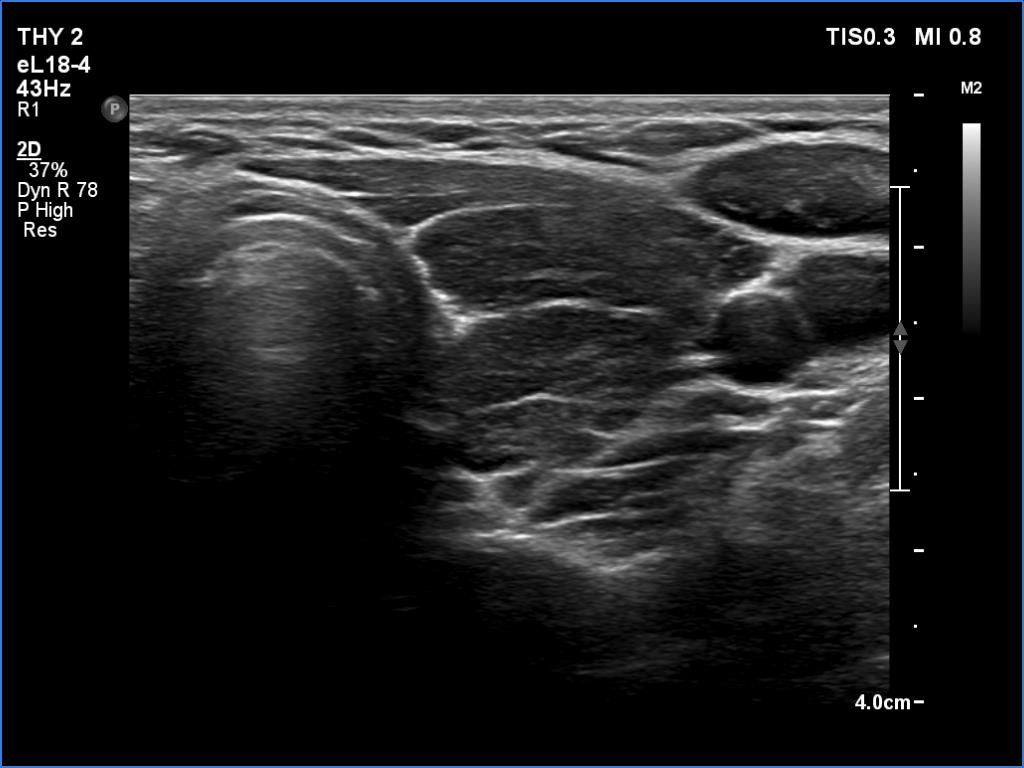

First examination (first row of images):

Clinical data: A 26-year-old woman at the 8th gestational week was referred for evaluation. She has been treated for hypothyroidism for 5 years.

Palpation: Both lobes were firm on palpation. No nodule could be palpated.

Laboratory tests: TSH 6.24 mIU/L, FT4 10.1 pM/L on daily 50 microgram levothyroxine.

Ultrasonography. The thyroid was echonormal and presented numerous hypoechogenic discrete areas. The echogenicity index was around 30% and 60%, right and left lobe, respectively. None of the discrete areas corresponded to pathological nodule.

Suggestion: to increase the dose of levothyroxine to daily 75 micrograms. Repeat TSH in 6 weeks.